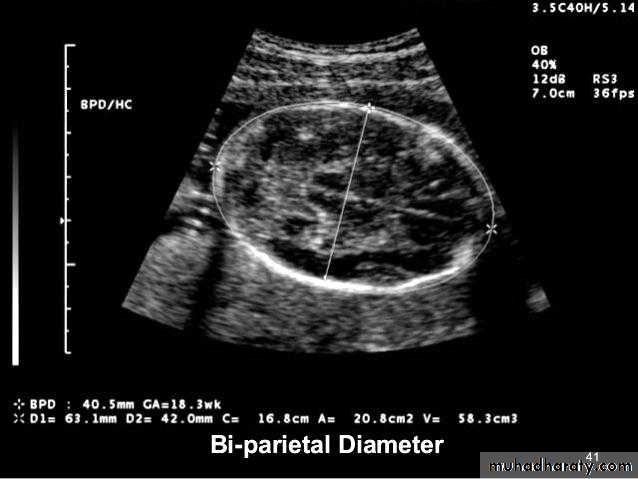

Mosul Medical College /radiology department2016BPD together with head circumference (HC), abdominal circumference (AC), and femur length (FL) are computed to produce an estimate of fetal weight. In the second trimester this may be extrapolated to an estimate of gestational age and an estimated due date (EDD) .

The BPD should be measured on an axial plane that traverses the thalami, and cavum septum pellucidum. The transducer must be perpendicular to the central axis of the head, and thus the hemispheres and calvaria should appear symmetric.